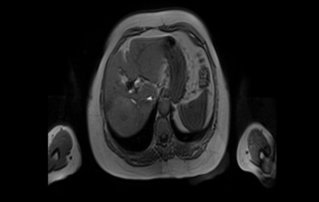

Female pelvic floor anatomy, which developed since the early 20th century, has had a variety of theories, including integral theory, three levels of vaginal support theory, "hammock hypothesis", and three-chamber system. Supporting structures such as pelvic floor muscles, fascia and ligament play an important role in maintaining the normal function of pelvic floor, among which levator ani muscle group is one of the most important supporting structures.